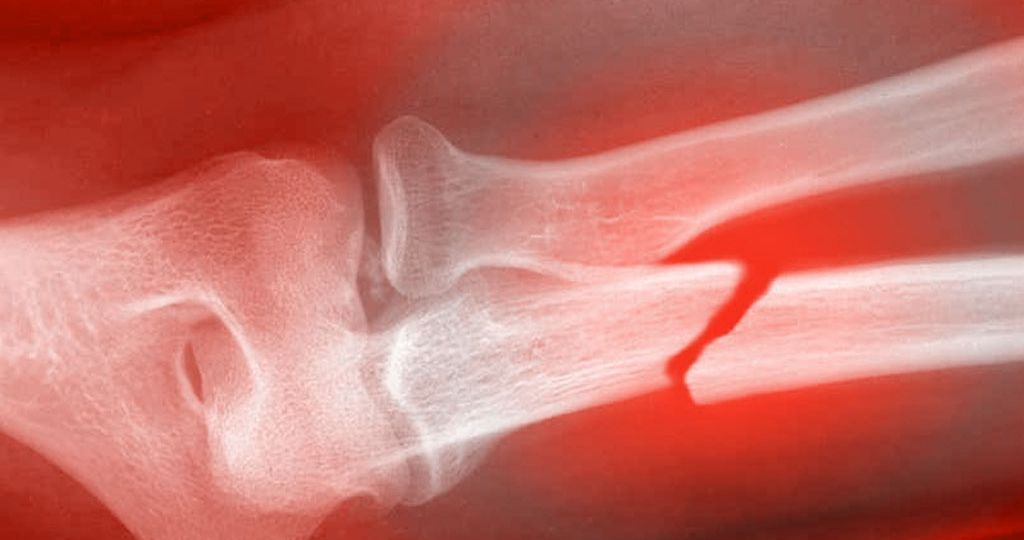

Studies on animals and humans have found that red and near infrared light therapy greatly aids in healing breaks, fractures, and bone defects. ATP production is interrupted in broken bones, and cells begin to die from lack of energy. Red and near infrared light have been shown to:

Overall, bone irradiated with near infrared wavelength show increase bone formation in collagen deposition. Read near infrared light therapy is becoming very popular in all sports wear brakes, sprains, and fractures are frequent.